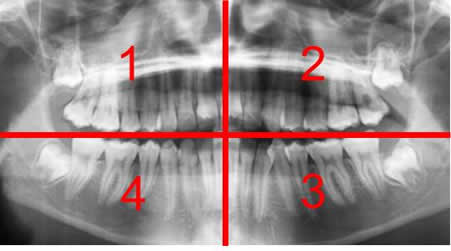

En Europa se dividen en 4 cuadrantes, numerados en sentido de las manecillas del reloj y empezando en el lado derecho del maxilar. Los 2 cuadrantes superiores, en el maxilar, (1 el derecho y 2 el izquierdo) y los 2 inferiores, en la mandíbula. (3 el izquierdo y 4 el derecho). (8). (Fig 10).

Fig 10. Numeración de las piezas.

Rx panorámica. División de la dentición en 4 cuadrantes.

1: Lado derecho del maxilar.

2: Lado izquierdo del maxilar.

3: Lado izquierdo de la mandíbula.

4: Lado derecho de la mandíbula.